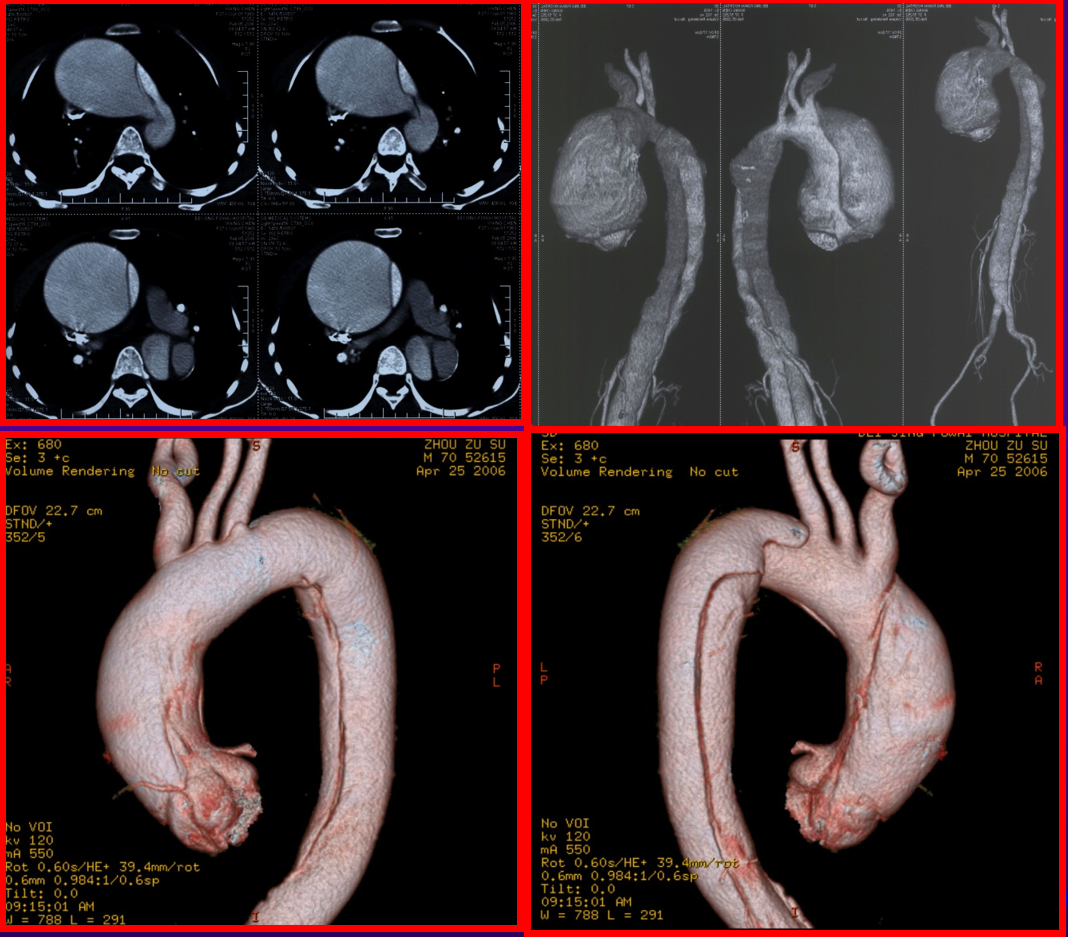

搏动性肿物:颈部、肢体或腹部摸到搏动性肿物,搏动频率与心跳相近,提示可能存在动脉瘤,如不及时治疗甚至会破裂危及生命。

急性胸背部疼痛:急性胸背部疼痛可能为夹层导致,发病突然,危险度高,病变常迅速向近端扩展导致心包填塞而致患者死亡,或向远端延伸阻塞主动脉的分支血管出现相应部位缺血,其中Stanford A型主动脉夹层24小时死亡率>35%,超过一半的患者在48小时内死亡,30天死亡率>95%。因此,尽早处理,选择合适的治疗方式是挽救生命的关键。TAAD单一的内科保守治疗效果不好,一经确诊,应积极手术治疗。

当您胸痛由肩背-胸背-腰腹-下肢转变时,且合并胸片纵膈增宽+化验检查D-二聚体升高,建议尽早血管外科就诊,急诊完善胸主动脉CTA。明确是否存在主动脉夹层。